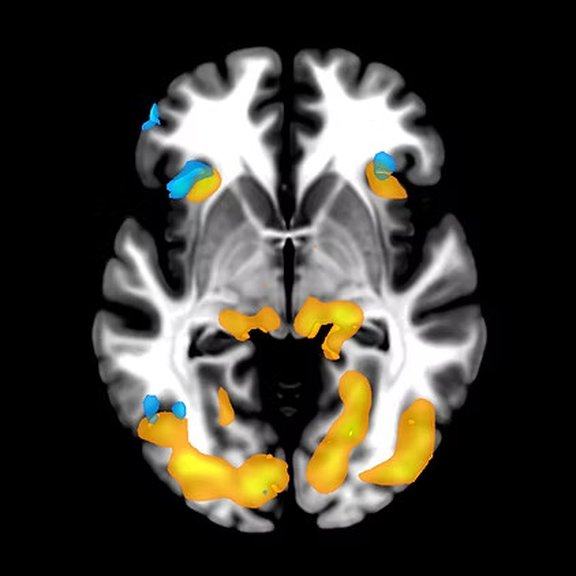

Functional magnetic resonance imaging (fMRI) measures brain activity by detecting changes related to blood flow in the brain. This technique is based on the fact that cerebral blood flow and neuronal activation are coupled. When an area of the brain is active, the blood flow in that region also increases. After statistical processing, this region can be highlighted on brain maps.